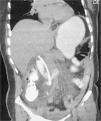

Mujer de 52 años de edad, previamente sana. Referida por coledocolitiasis difícil, documentada durante colecistectomía abierta con exploración de vía biliar y colocación de sonda en T. En nuestro hospital se realizó colangiopancreatografía retrógrada endoscópica (CPRE), con colocación de endoprótesis plástica (10Fr×12cm) y retirada de la sonda en T. La paciente acudió a urgencias 12h posteriores a la CPRE con abdomen agudo. Durante el abordaje se encontraron datos de respuesta inflamatoria sistémica, y en la tomografía computarizada de abdomen se observó la endoprótesis biliar con el extremo proximal en la vía biliar y el extremo distal perforando la tercera porción del duodeno (fig. 1). Se realizó panendoscopia corroborando el sitio de perforación de la endoprótesis (fig. 2). La paciente requirió laparotomía con extracción de la endoprótesis, cierre primario de la perforación duodenal (fig. 3), exploración de vía biliar con resolución de la coledocolitiasis y verificación con colangioscopia transoperatoria (fig. 4). Las perforaciones duodenales por endoprótesis no están consideradas en la clasificación de Stapfer1. Estas perforaciones son raras (1%), y se deben a la migración de la prótesis (lo cual ocurre en el 8-10% de los casos)2. La mayoría de los reportes de caso han ocurrido en prótesis mayores a 10Fr×12cm2,3. El tratamiento es endoscópico en ausencia de peritonitis o quirúrgico en pacientes con colecciones retroperitoneales, sepsis y peritonitis1,2.